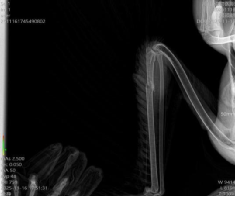

对黑颈鹤进行DR检查           DR显示黑颈鹤左侧尺骨骨折

16日,越西县林业和草原局艾永斌一行将黑颈鹤送到西昌学院攀西动物医院,郝桂英快速组织严光文教授、黄增文博士、常卫华、赵影、李昊、李欣虹等专家对黑颈鹤进行诊疗处置,经DR检查、临床检查等内容,确诊黑颈鹤左侧尺骨骨折,左侧腕关节擦伤